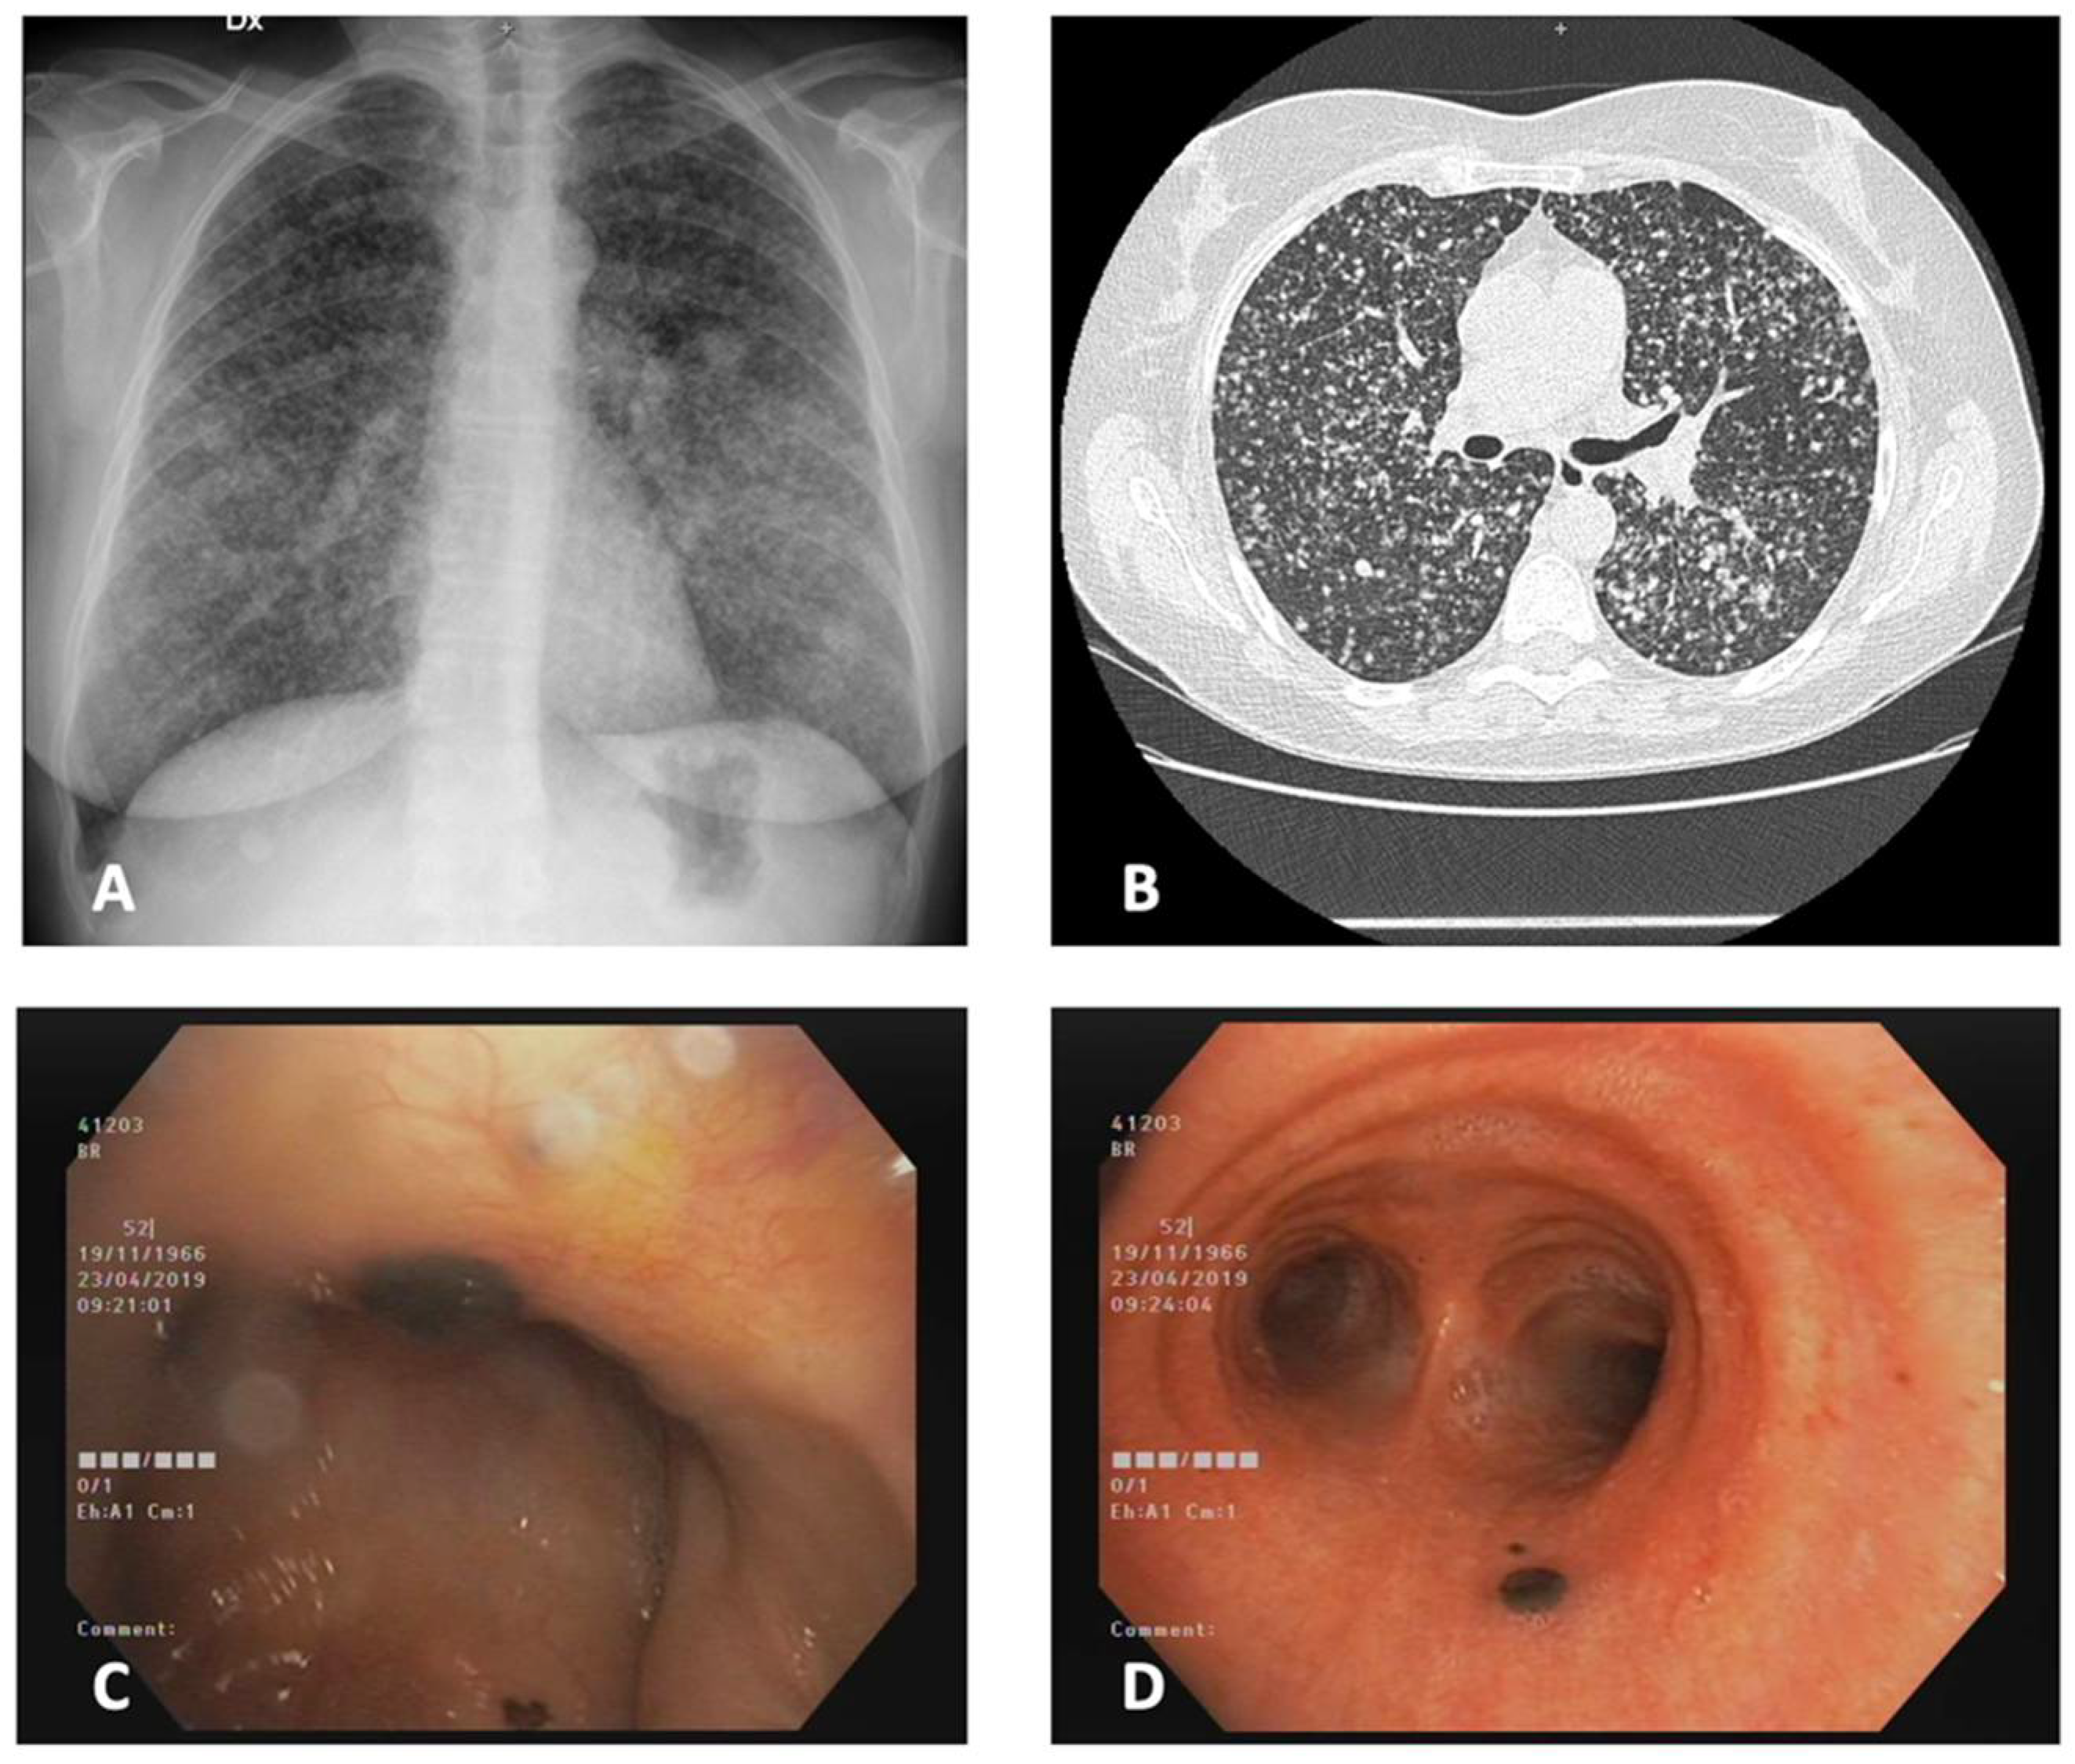

3.1. Case 1

3.2. Case 2

3.3. Case 3

3.4. Case 4